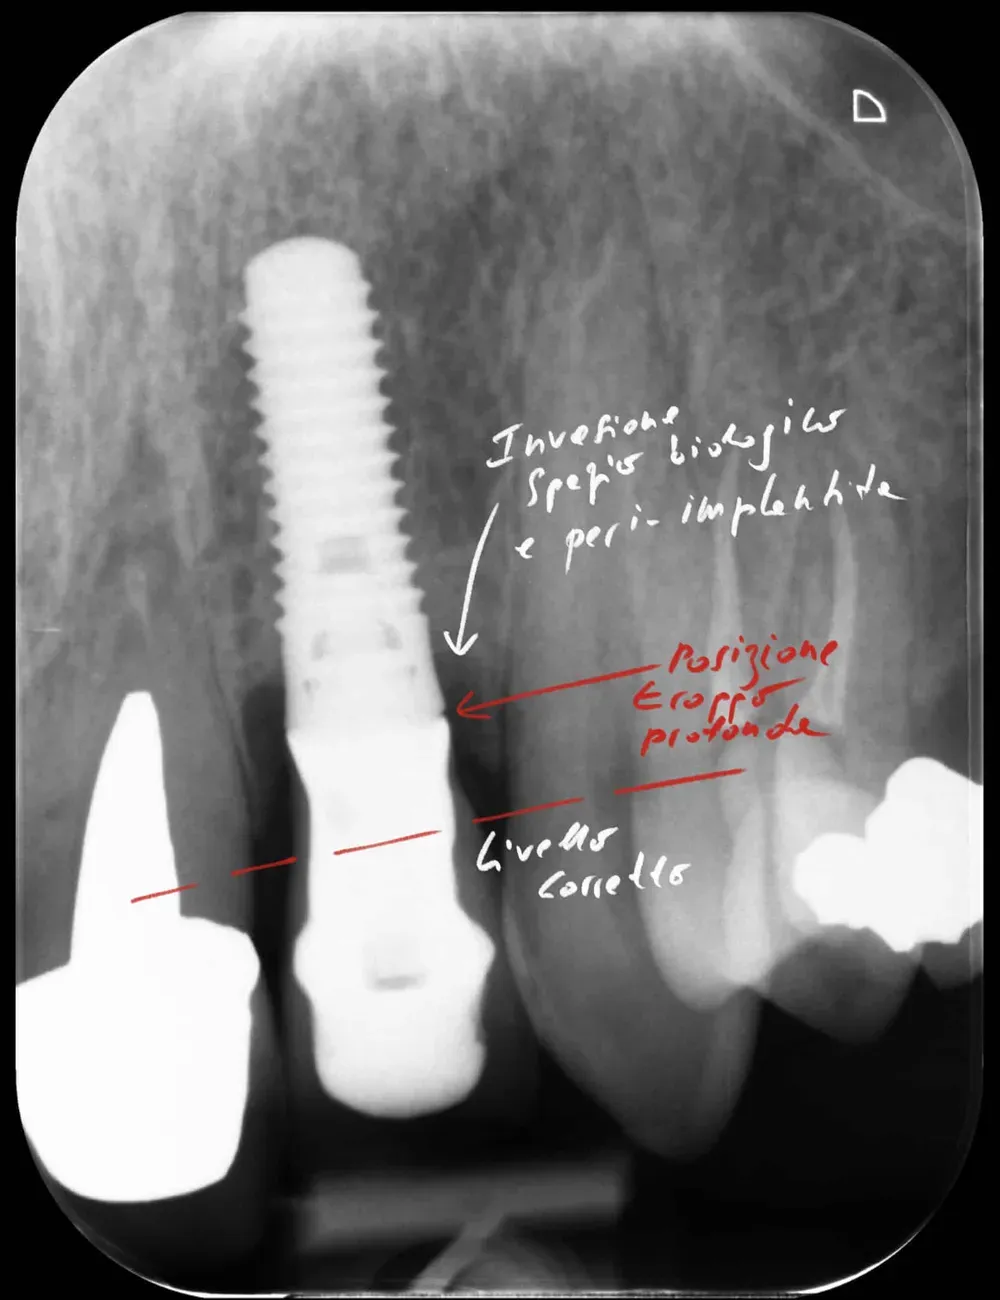

Altezza dell’abutment

La review di Laleman e Lambert dedica attenzione a due parametri spesso trascurati: il profilo di emergenza e l’altezza dell’abutment.

Sull’altezza: la review di Muñoz e collaboratori (https://doi.org/10.1111/clr.14025), basata solo su RCT, ha identificato una soglia di 2 mm. Abutment alti almeno 2 mm svolgono un ruolo protettivo contro la perdita ossea marginale, permettendo la formazione dell’adesione mucosale sovracrestale. Questo effetto appare indipendente dallo spessore dei tessuti molli, anche se in caso di tessuti sottili è importante posizionare gli impianti sottocrestali (o meglio, “infracrestali”) per consentire la formazione del complesso mucosale sovracrestale.

La regola dei 4mm di Linkevičius ci viene in aiuto per stabilire la posizione verticale che protegge l’impianto dal riassorbimento osseo, sempre nel caso di connessioni affidabili dal punto di vista batteriologico. Nelle prossime immagini, dei monconi protesici relativamente lunghi su impianti a connessione conica, testimoniano l’ottimo risultato reale di questo concetto, con impianti perfettamente integrati e privi di infiltrazione infiammatoria, anche in condizioni ossee impegnative.

Saper leggere la radiografia

Chi ha l’occhio allenato sa che il destino di un impianto è spesso scritto già nelle radiografia post-operatoria. Si vedono i punti dove la struttura non calza. Dove le tensioni meccaniche sono eccessive. Dove il collega ha forzato con il cacciavite per fare entrare la protesi.

In quelle zone la biologia non perdona: la tensione si traduce in riassorbimento osseo, e lo spazio non sigillato diventa il nido perfetto per i batteri (l’osseointegrazione è un equilibrio delicato). Gli anaerobi gram-negativi, i nostri nemici, amano questi spazi chiusi, lontani dalla luce, dall’ossigeno e dal sangue. Per chi sa interpretare questi segnali, la peri-implantite futura non è un’ipotesi. È una diagnosi anticipata.

Per concludere il confronto tra le varie connessioni, l’immagine che segue è una radiografia con due impianti affiancati: un tissue-level ben posizionato fatto da un collega anni addietro e un impianto a connessione conica in posizione infracrestale con abutment della corretta lunghezza per il caso. Il secondo è un mio caso. È interessante notare come il cono dello spazio biologico sia identico. Se ben posizionati, tutti gli impianti funzionano egregiamente (l’impianto più vecchio inizia a soffrire un pochino, ma questa è un’altra storia).